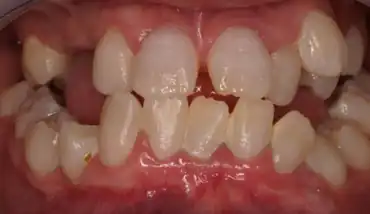

Clinically the teeth look normal in colour and morphologic appearance; however, they are commonly very mobile and exfoliated prematurely.[3]

Both primary and permanent dentitions can be affected by either type I or type II dentin dysplasia. However, deciduous teeth affected by type II dentin dysplasia have a characteristic blue-amber discolouration, whilst the other dentition appears normal.[3]

Type I: Radicular type

Type I has been known as radicular dentine dysplasia because the teeth have undeveloped root(s) with abnormal pulp tissue. Morphology and colour of the crown mostly appear normal, but occasionally teeth appear slightly amber coloured or bluish-brown shine in primary teeth with no or only immature root development. The teeth are mostly maligned and have higher risk of fracture.[12]